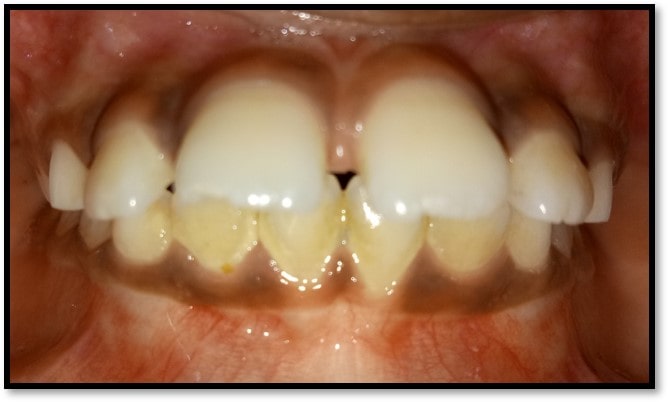

We at the Department of Pediatric & Preventive Dentistry focus on comprehensive oral health care needs of a child from infancy to adulthood and provide comprehensive, therapeutic as well as preventive care to all children including those with special care needs.

- Proposed a modification of Angle’s classification for application in primary dentition and various cross sectional studies have been carried out to validate its application.